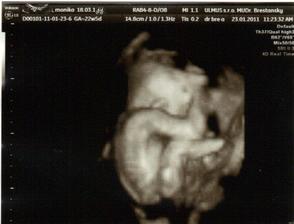

✿♥♥♥♥Bude to dievčatko!!!!! ♥♥♥♥✿

Bude to Stella 🙂

krasne 3D sono 🙂